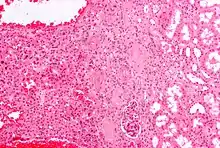

Micrograph of a renal oncocytoma.

Histologic appearance

An oncocytoma is an epithelial tumor composed of oncocytes, large eosinophilic cells having small, round, benign-appearing nuclei with large nucleoli and excessive amounts of mitochondria.